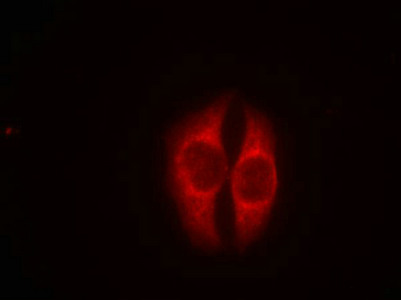

應用范圍:ELISA,WB,IF

Application Recommended Dilution WB 1:500-1:1000 IF 1:100-1:200 -

相關(guān)疾?。?/div>Esophageal cancer (ESCR); Li-Fraumeni syndrome (LFS); Squamous cell carcinoma of the head and neck (HNSCC); Lung cancer (LNCR); Papilloma of choroid plexus (CPP); Adrenocortical carcinoma (ADCC); Basal cell carcinoma 7 (BCC7)亞細胞定位:Cytoplasm. Nucleus. Nucleus, PML body. Endoplasmic reticulum. Mitochondrion matrix. Cytoplasm, cytoskeleton, microtubule organizing center, centrosome.; [Isoform 1]: Nucleus. Cytoplasm. Note=Predominantly nuclear but localizes to the cytoplasm when expressed with isoform 4.; [Isoform 2]: Nucleus. Cytoplasm. Note=Localized mainly in the nucleus with minor staining in the cytoplasm.; [Isoform 3]: Nucleus. Cytoplasm. Note=Localized in the nucleus in most cells but found in the cytoplasm in some cells.; [Isoform 4]: Nucleus. Cytoplasm. Note=Predominantly nuclear but translocates to the cytoplasm following cell stress.; [Isoform 7]: Nucleus. Cytoplasm. Note=Localized mainly in the nucleus with minor staining in the cytoplasm.; [Isoform 8]: Nucleus. Cytoplasm. Note=Localized in both nucleus and cytoplasm in most cells. In some cells, forms foci in the nucleus that are different from nucleoli.; [Isoform 9]: Cytoplasm.蛋白家族:P53 family組織特異性:Ubiquitous. Isoforms are expressed in a wide range of normal tissues but in a tissue-dependent manner. Isoform 2 is expressed in most normal tissues but is not detected in brain, lung, prostate, muscle, fetal brain, spinal cord and fetal liver. Isoform 3數(shù)據(jù)庫鏈接: